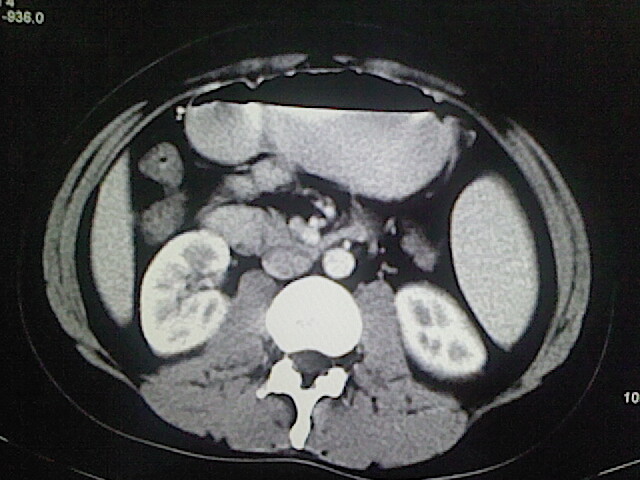

以下是引用卜一在2009-3-14 9:49:00的发言:[br]胆囊萎缩,胆囊壁不规则增厚,内部结构模糊,增强明显强化。另:肝左叶外侧段肝囊肿。支持:慢性胆囊炎!高度可疑:胆囊癌!

以下是引用余辉在2009-3-14 8:48:00的发言:[br]1)慢性胆囊炎。2)肝左叶外侧段肝囊肿。3)脂肪肝。[br]支持,胆囊萎缩,密度增高,不知b超具体有何提示,钙胆汁?结石?

以下是引用jiangjing在2009-3-14 10:18:00的发言:[br]1)慢性胆囊炎。2)肝左叶外侧段肝囊肿。3)脂肪肝。4.】建议行肝功能检查